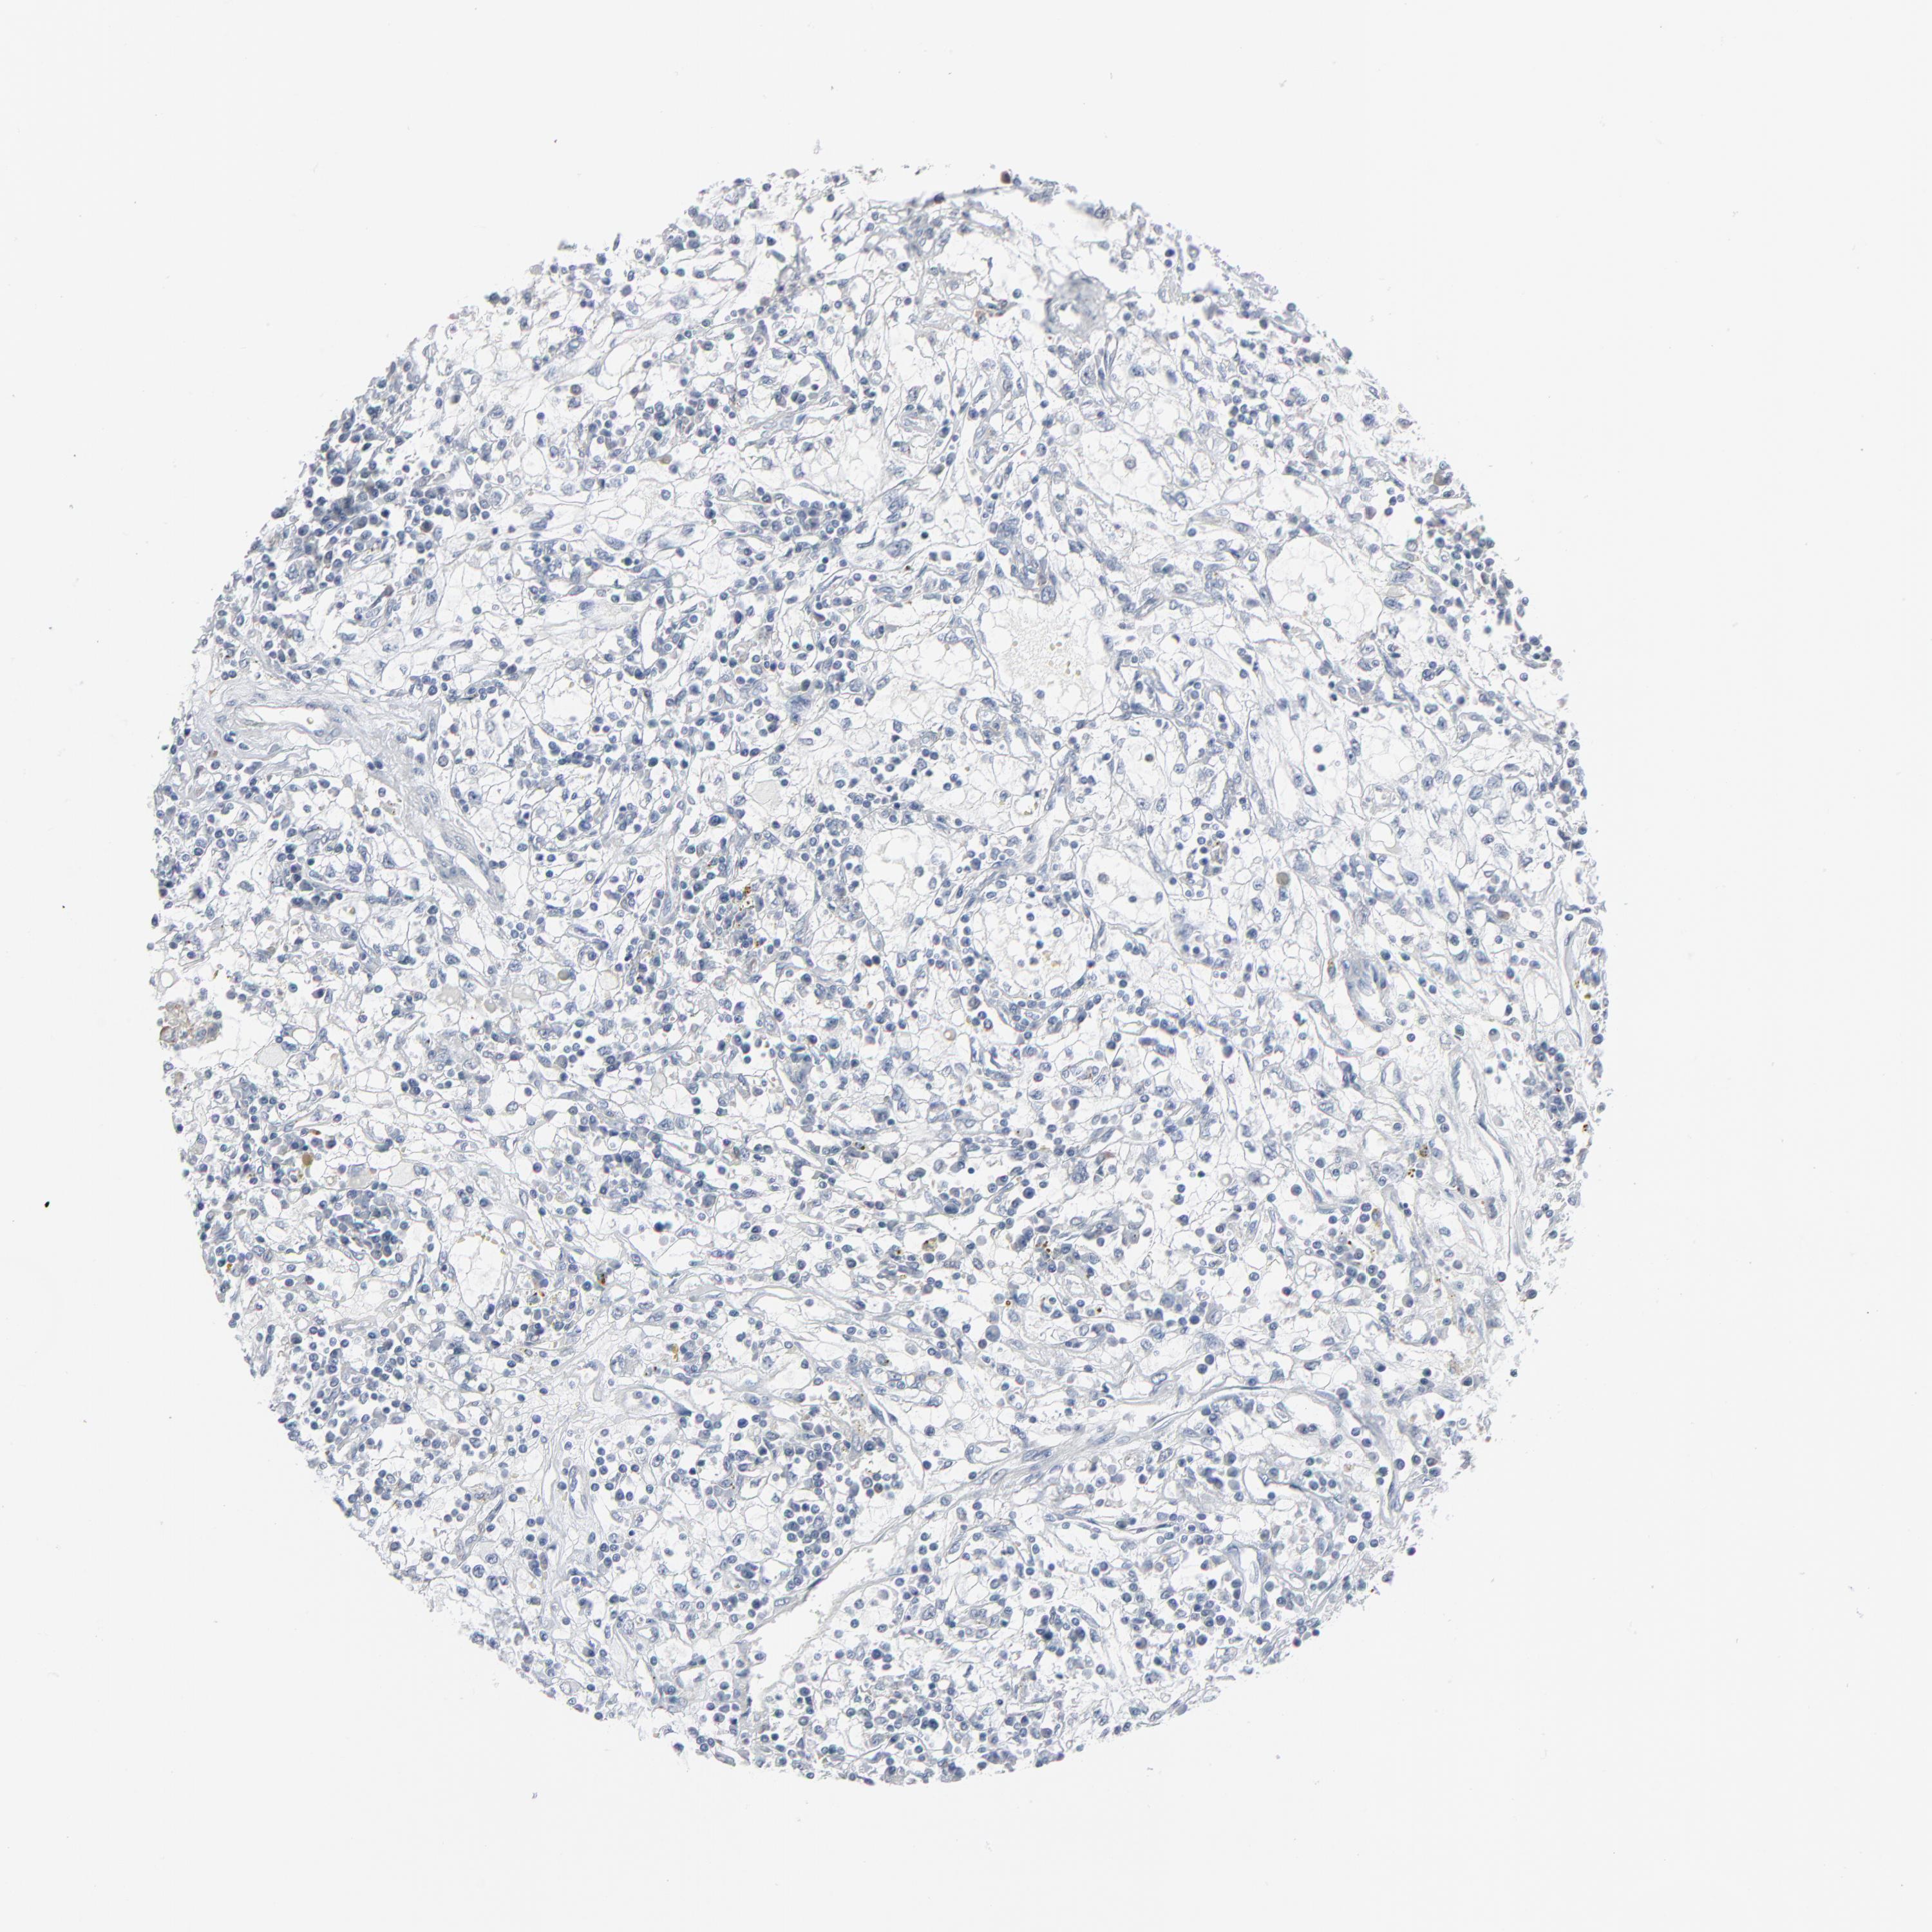

KIDNEY RENAL CLEAR CELL CARCINOMA (VALIDATION) - Interactive survival scatter ploti

The Survival Scatter plot shows the clinical status (i.e. dead or alive) for all individuals in the patient cohort, based on the same data that underlies the corresponding Kaplan-Meier plots. Patients that are alive at last time for follow-up are shown in blue and patients who have died during the study are shown in red.

The x-axis shows the expression levels (FPKM) of the investigated gene in the tumor tissue at the time of diagnosis. The y-axis shows the follow-up time after diagnosis (years). Both axes are complimented with kernel density curves demonstrating the data density over the axes. The top density plot shows the expression levels (FPKM) distribution among dead (red) and alive patients (blue). The right density plot shows the data density of the survived years of dead patients with high and low expression levels respectively, stratified using the cutoff indicated by the vertical dashed line through the Survival Scatter plot. This cutoff is automatically defined based on the FPKM cutoff that minimizes the p-score. The cutoff can be changed by dragging the vertical line or by entering a cutoff value in the square labeled "Current cut-off".

Under the Survival Scatter plot the p-score landscape (black curve; left axis) is shown together with dead median separation (red curve; right axis). Dead median separation is the difference in median mRNA expression between patients who have died with high and low expression, respectively. It is calculated as follows: median FPKM expression of dead patients with high expression - median FPKM expression of dead patients with low expression. This is intended to aid the user in visually exploring custom cutoffs and the associated p-scores and dead median separation.

Individual patient data is displayed and can be filtered by clicking on one or more of the category buttons on the top of the page. Categories describing expression level and patient information include: high, low, alive, dead, female, male and tumor stages. The scale of the x-axis can be toggled between linear and log-scale by clicking on the "x log" button. Mouse-over function shows TCGA ID, patient information and mRNA expression (FPKM) for each patient.

& Survival analysisi

Kaplan-Meier plots summarize results from analysis of correlation between mRNA expression level and patient survival. Patients were divided based on level of expression into one of the two groups "low" (under cut off) or "high" (over cut off). X-axis shows time for survival (years) and y-axis shows the probability of survival, where 1.0 corresponds to 100 percent.

PHGDH is not prognostic in Kidney Renal Clear Cell Carcinoma (validation)

Best expression cut offi

Based on the FPKM value of each gene, patients were classified into two groups and association between prognosis (survival) and gene expression (FPKM) was examined. The best expression cut-off refers the FPKM value that yields maximal difference with regard to survival between the two groups at the lowest log-rank P-value. Best expression cut-off was selected based on survival analysis .

When clicking on this number, the vertical dashed line indicating cut-off, the interactive survival plot, and the Kaplan-Meier curve will be adjusted to show results based on the best expression cut-off.

: 3.78

Average pTPM 21.4

Number of samples 100